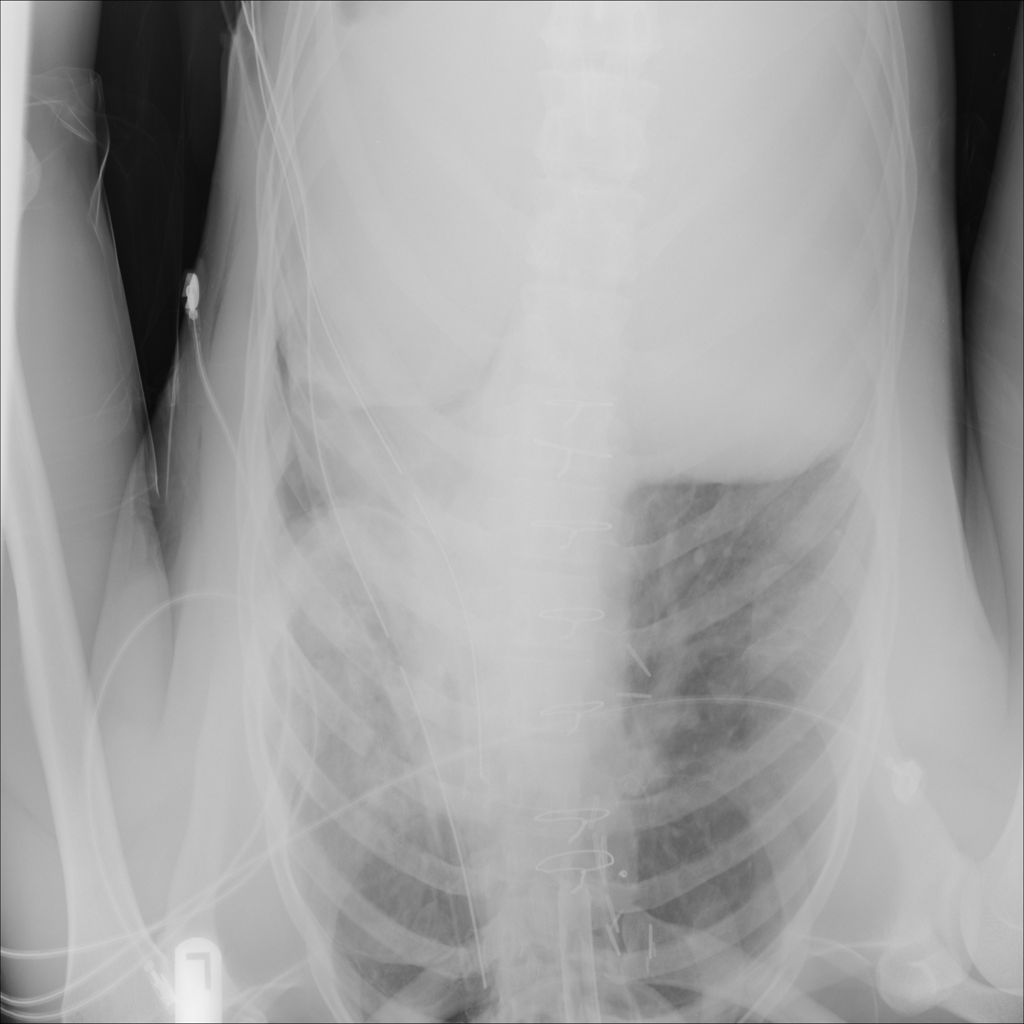

Showing up to 90 reference images for Pneumothorax.

PAT-4639 · IMG-011Pneumothorax

PAT-4639 · IMG-011

AP